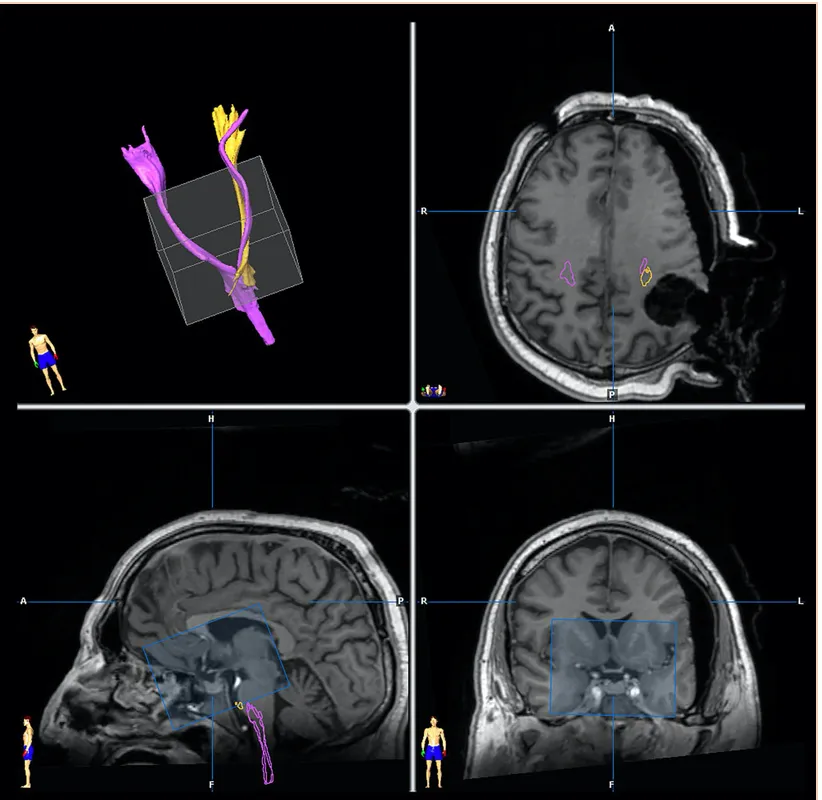

保护重要功能结构:术中成像能描绘出肿瘤相邻的功能结构,特别是在使用DTI纤维束重建时,进而避免“误伤”重要功能组织。

图:低级别胶质瘤的术中iMRI成像。进行了术前皮质脊髓束(CST)(粉红色)和术中(黄色)图像的纤维追踪:由于肿瘤切除后的移位,注意CST的不同位置非常重要。